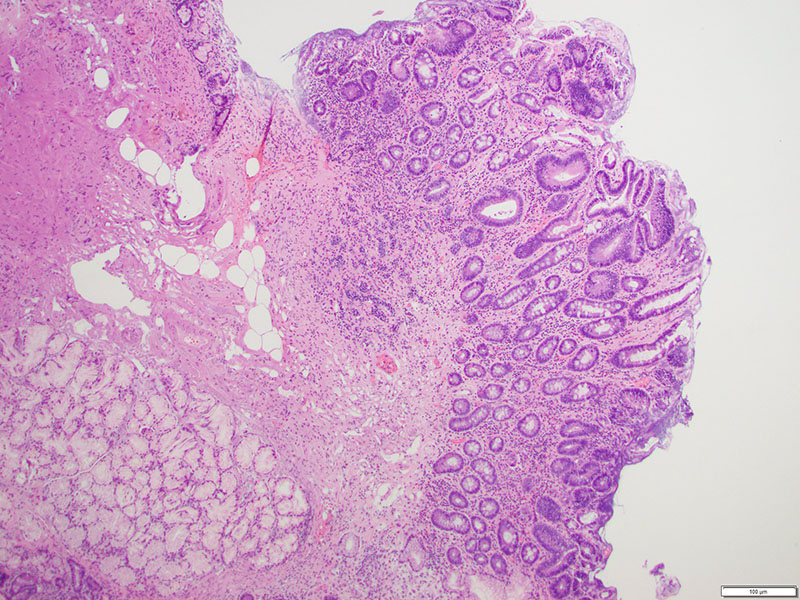

The patient is sent for an esophagogastroduodenoscopy (EGD), which reveals a 2 c.m. polyp in the third segment of the duodenum. Biopsy confirms duodenal adenoma, for which the patient elects to undergo an EGD with endoscopic mucosal resection (EMR).Microscopic examination demonstrates duodenal mucosa with low-grade epithelial dysplasia overlying foci of bland, monotonous cells with scant cytoplasm (Figures 1 & 2). The cells are arranged in nests and trabeculae that infiltrate into the superficial muscularis mucosae (Figure 3). Immunohistochemistry shows positive staining for synaptophysin (Figure 4) and chromogranin (Figure 5), as well as a Ki-67 labeling index < 1% (Figure 6).